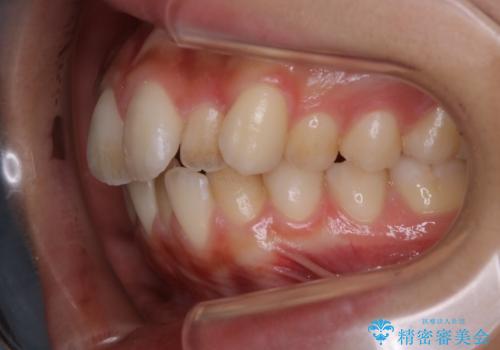

初診時の歯並びの状態としては、上下ともに全体に及ぶの中等度のがたつき(叢生)があり、全特に左上の前歯は1本だけ引っ込んでいる状態でした。